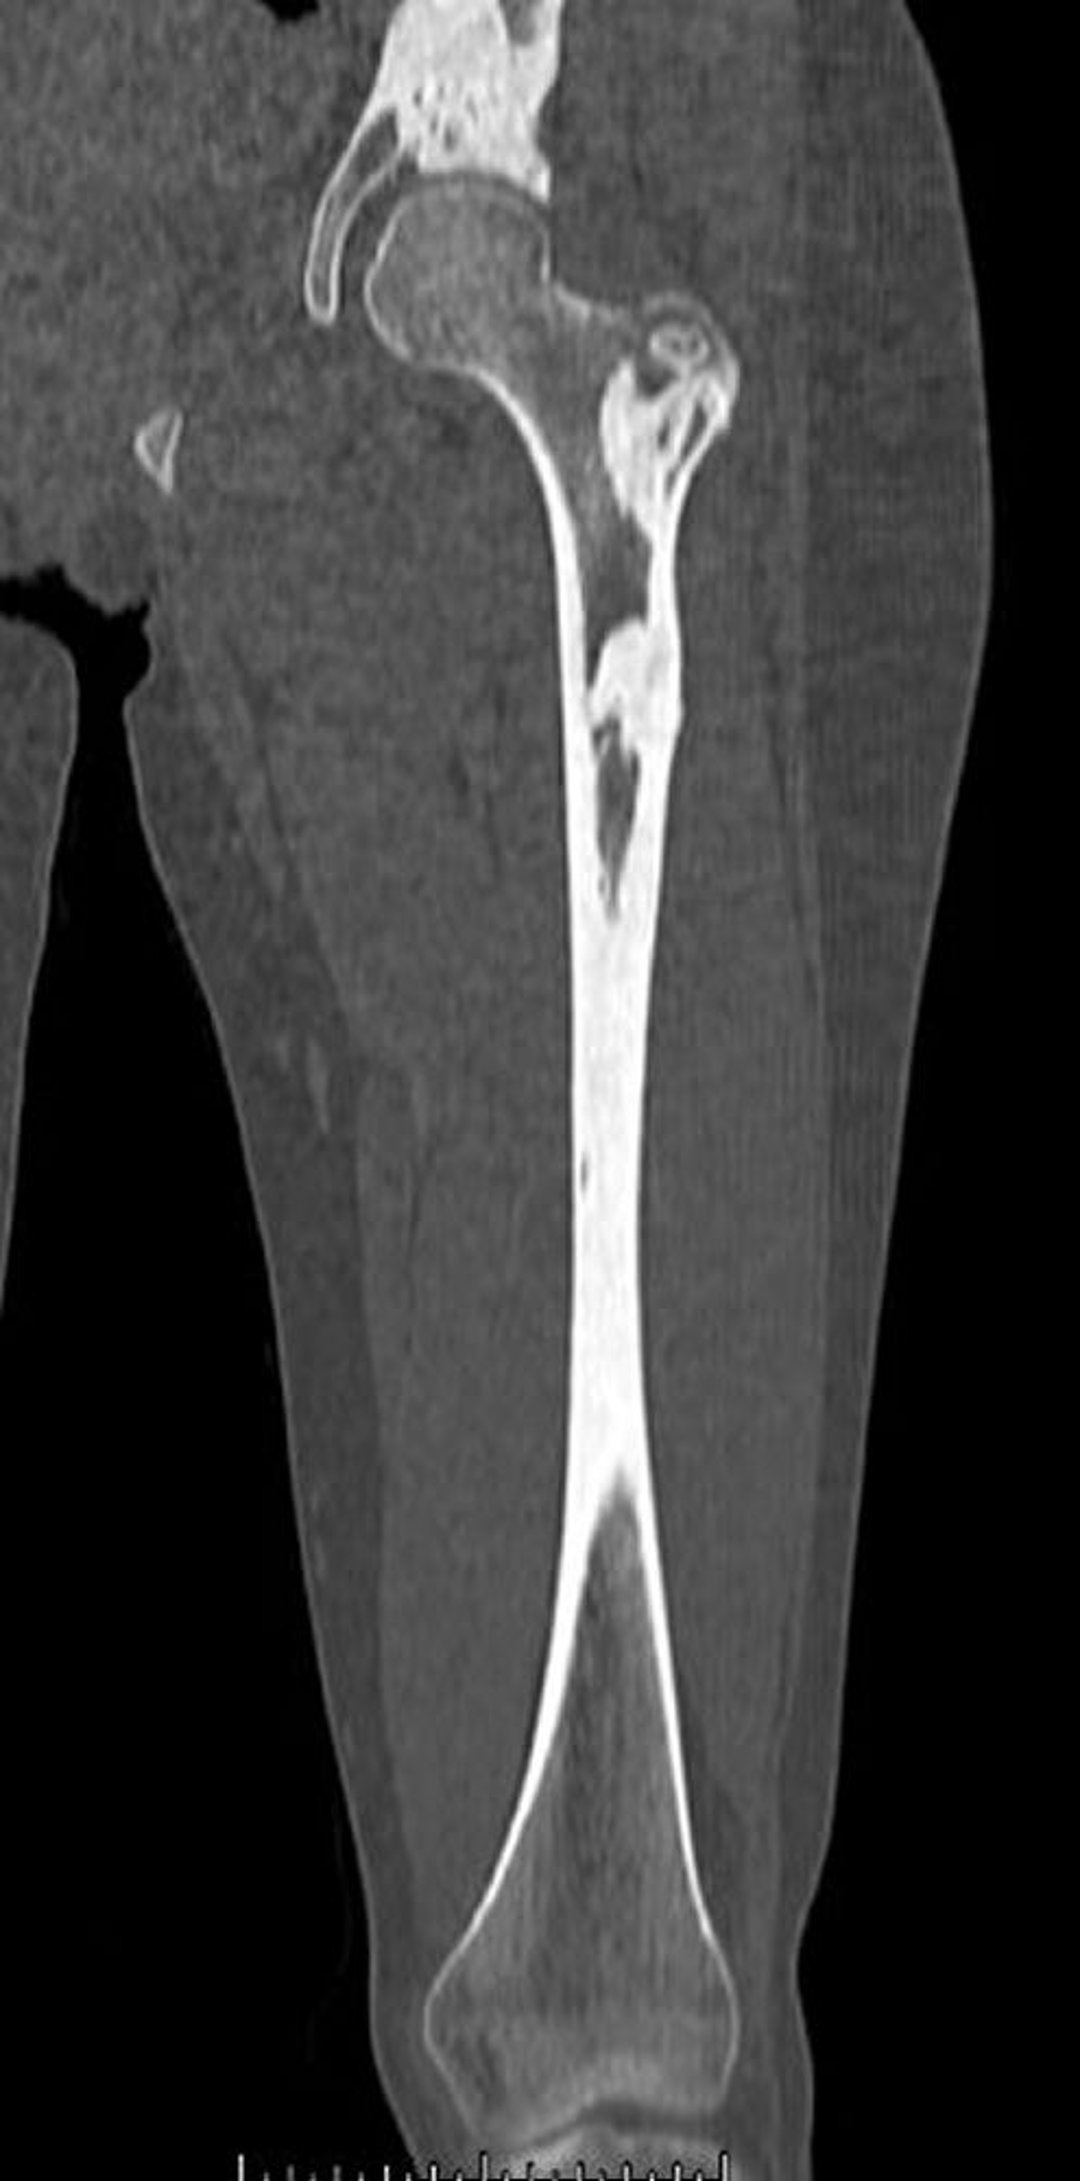

Mélorhéostose (TDM)

Cette TDM montre les lésions osseuses denses de mélorhéostose dans le fémur et le bassin.

Image courtoisie de Michael J. Joyce, MD, and David M. Joyce, MD.